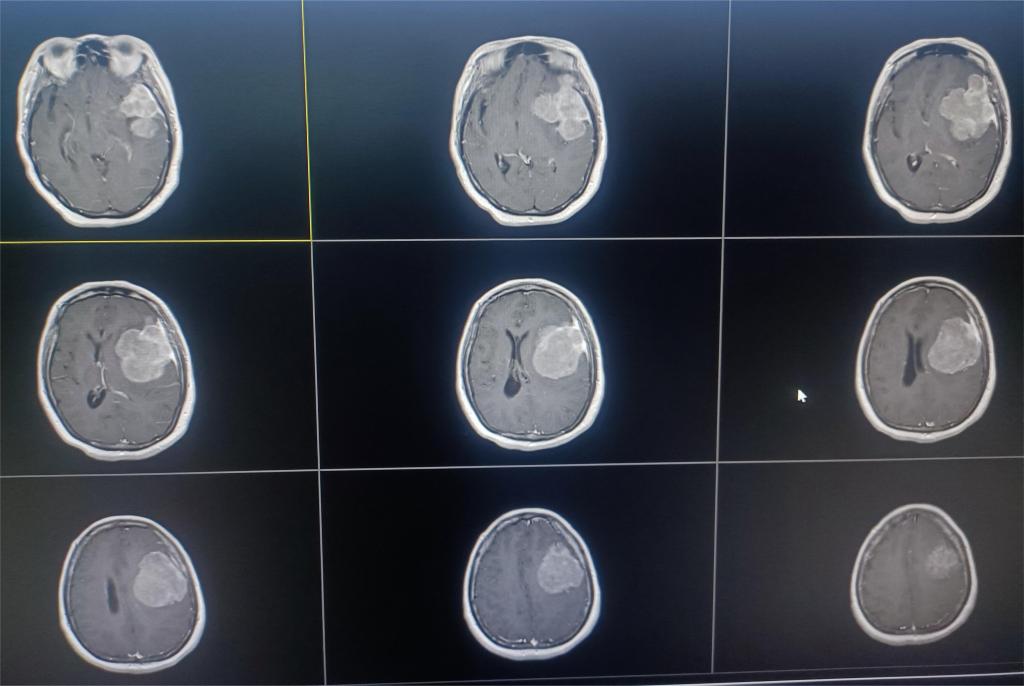

手术过程中,可见巨大肿瘤组织对正常脑组织压迫明显,局部与重要血管关系密切,在医护团队的密切配合及精细操作下,最终成功将肿瘤完整切除(图二)。

图二

术后病理回报显示:脑膜上皮型脑膜瘤(WHO I级),患者症状完全消失,恢复良好。